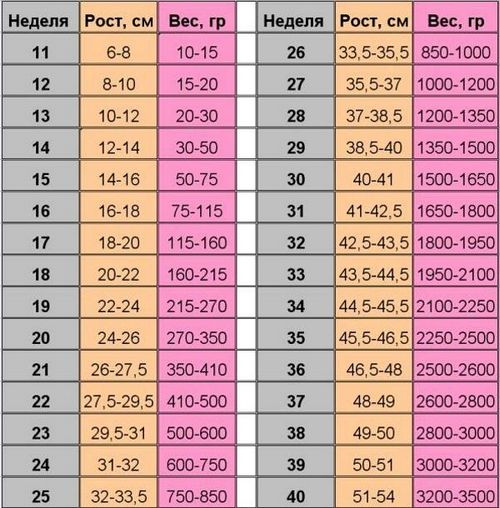

Таблиця ваги плоду по тижнях вагітності

Доктора, спираючись на результати численних досліджень, змогли скласти таблицю, в якій вказується маса виношуваної малюка на різних термінах його перебування в утробі матері. Дані, наведені в таблиці - це вирахувані середні показники, які спостерігаються в більшості випадків. Оскільки є безліч факторів, що впливають на розвиток плода. в таблиці вказуються верхні і нижні межі ваги і зростання.

Коли жінка проходить УЗД при вагітності. доктора визначають вагу виношуваної малюка і зіставляють з даними таблиці. Це дозволяє виявити наявність відхилень в показниках маси і призначити жінці відповідне обстеження, щоб визначити їх причину.

На ранніх термінах виношування вага малюків майже завжди тримається в чітко визначеному діапазоні, тому лікарі навіть при несуттєве відхилення отриманих даних від показників таблиці, починають шукати причину такої ситуації. Набагато складніше визначити наявність проблем на більш пізніх термінах вагітності. В кожному окремому випадку вага малюка може значно відрізнятися від наведених у таблиці даних, і це не завжди є наслідком розвитку хвороб.

Для докторів велике значення має динаміка збільшення маси малюка. Показники ваги в кожному конкретному випадку рідко можуть чітко вказувати на наявність захворювань або патологій. Більш того, у кожної клініки є своя таблиця вагітності по тижнях, що свідчить про ненадійність показників для діагностування будь-якої проблеми, пов'язаної з розвитком виношуваної дитини.

Норми ваги виношуваної малюка по тижнях вагітності